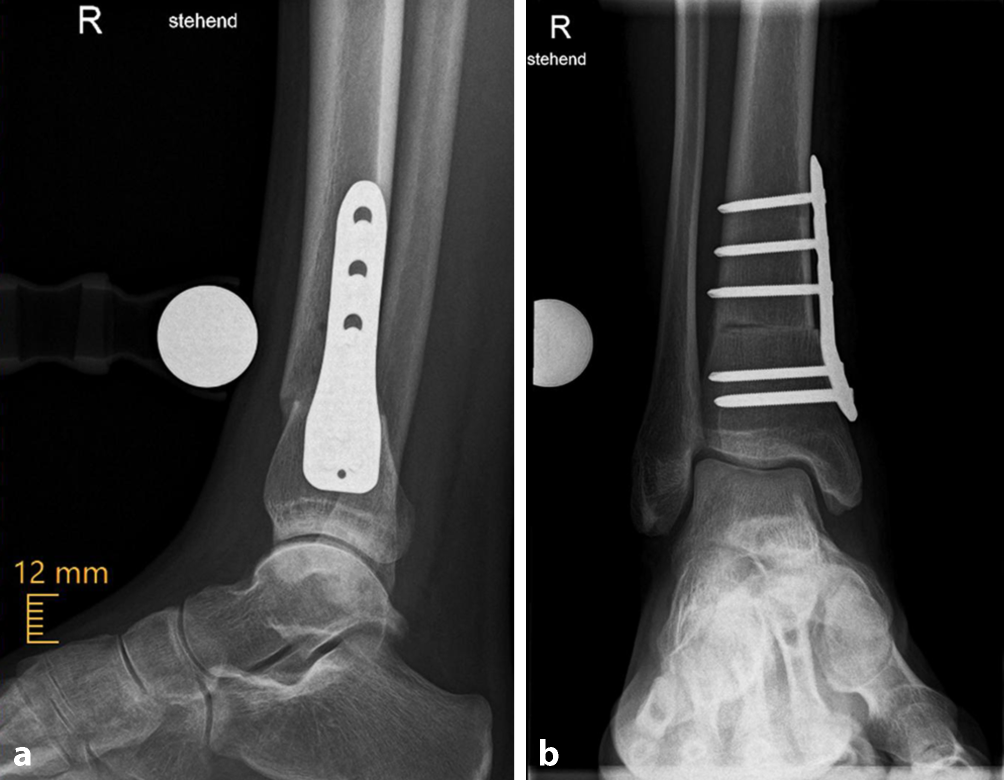

Im hier beschriebenen Fallbeispiel konnte die Nachbehandlung wie geplant durchgeführt werden, und der anteriore Knieschmerz war nach durchgeführtem Belastungsaufbau 3 Monate postoperativ verschwunden. Das klinische Gangbild zeigt zu diesem Zeitpunkt eine antegrad gerichtete Patella und weiterhin gerade Fußprogressionsachse. Das stehende Röntgenbild des oberen Sprunggelenks 3 Monate postoperativ zeigt eine unveränderte Osteotomie‑, Platten- und Schraubenlage (Abb. 5).

Abb. 5

Röntgenaufnahme des oberen Sprunggelenks (OSG) 3 Monate postoperativ. a Laterale Projektion, b anteroposteriore Projektion, mit einem a.-p. medial flauer abgrenzbaren Osteotomiespalt ohne sekundäre Dislokation mit regelrechter Materiallage. (Mit freundl. Genehmigung, © T. Tondelli et al.)